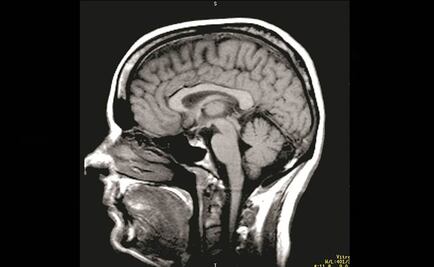

El ser humano produce nuevas neuronas que le permiten olvidar y refrescar la memoria, reporta investigador de la UNAM

Investigación podrá ayudar a entender mejor enfermedades como epilepsia o alzheimer

Síntoma inicial del deterioro cognitivo en esa población es la pérdida de la memoria